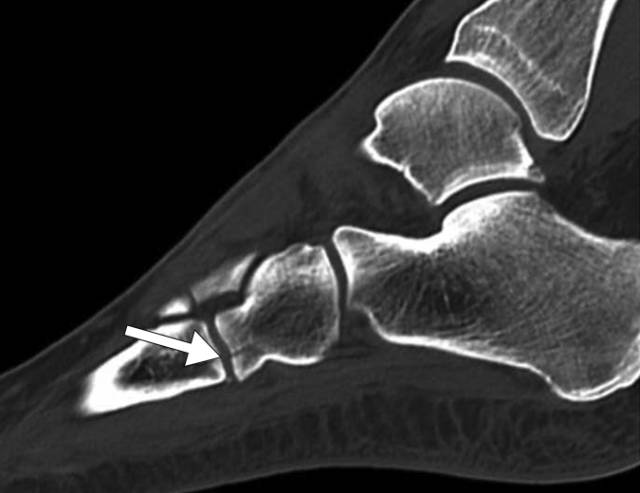

图5 -53岁男性骨折骨折。C,随后的矢状(C)和轴向(D)CT图像更全面地显示通过延伸到距下关节的距骨的身体的另外的倾斜骨折(箭头)。

图5 -53岁男性骨折骨折。A,前后(A)和外侧(B)X线照片显示粉碎的内侧骨折体骨折。B,前后(A)和外侧(B)X线照片显示粉碎的内侧骨折体骨折。